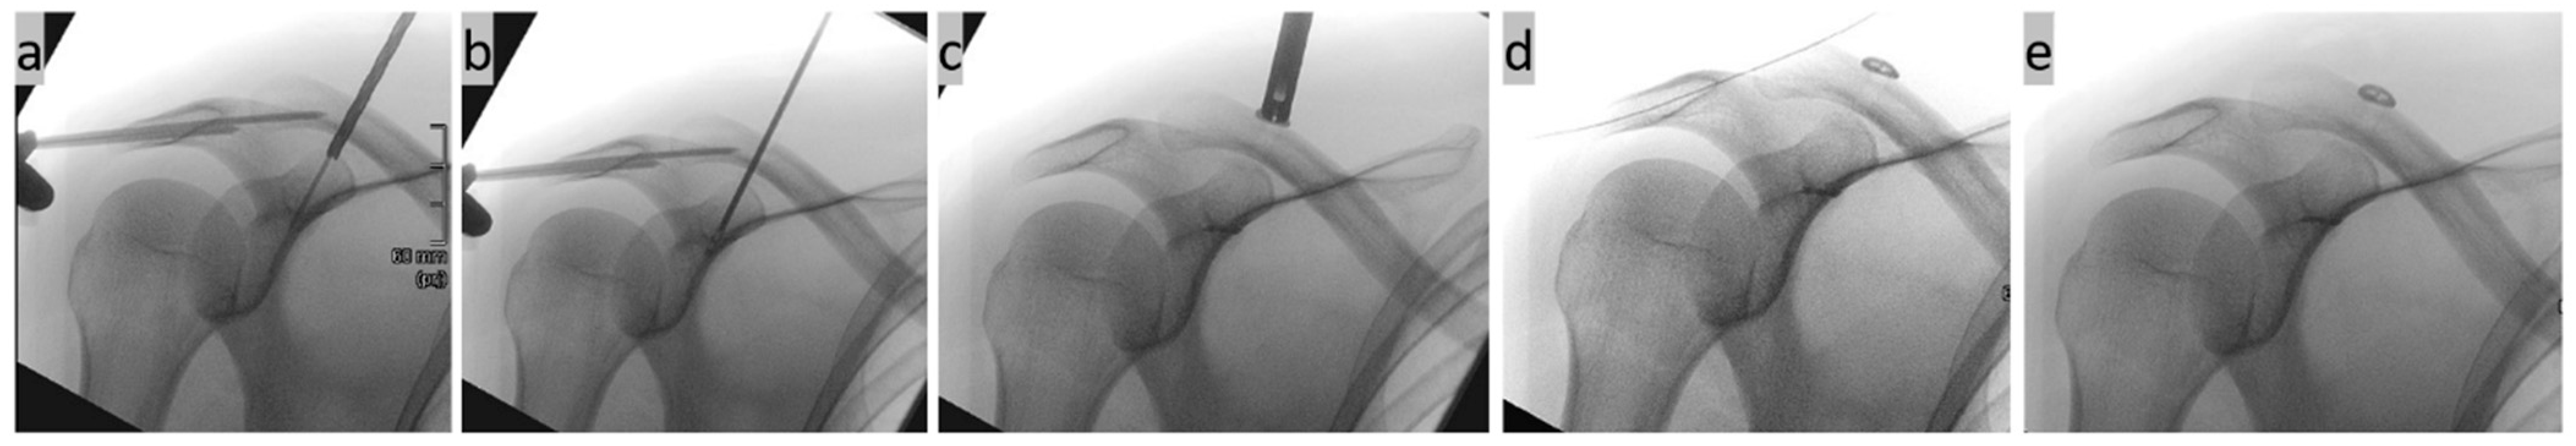

2. Surgical Technique

- Böhringer, A.; Gebhard, F.; Dehner, C.; Eickhoff, A.; Cintean, R.; Pankratz, C.; Schütze, K. 3D C-arm navigated acromioclavicular joint stabilization. Arch. Orthop. Trauma. Surg. 2023, 144, 601–610. [Google Scholar] [CrossRef]